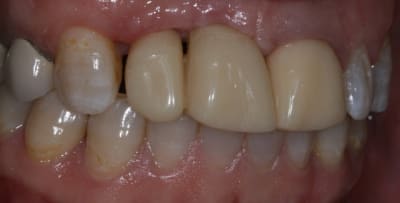

On avance dans le cas, j'ai revu la patiente hier.

Elle est satisfaite et moi pas vraiment, comme quoi...

Elle ne veut pas faire de chir mucco gingivale et accepte éventuellement que je fasse une petite chir d'élongation coronaire sur 21 car elle trouve cela surperflux.

Tristesse et difficulté des sourires gingivaux !

J'avais bien raison de me méfier au départ...

Dommage pour la teinte...

Une greffe osseuse aurait bcp aider, les implants sont trop enfouis par rapport à la 21.

Je suis persuadé que si ton prothèsiste réussit à reproduire la richesse des petits défauts de ses propres dents sur tes dents en céramique , ce serait et ça passerait bcp mieux

Je crois que finalement ces trois trop jaune et quasi monolithique ds leur couleur est vraiment la chose la plus atroce

Bon finalement je vous poste le cas terminé.

La prochaine fois je ferrai une greffe d'apposition comme j'avais pu le préssentir... Ca me permettra de garder les papilles.

A la prochaine séance je gomme la coloration mésiale de 12, c'est promis ;+)

Un cas pas évident... l'important est que la patiente soit contente à la fin.